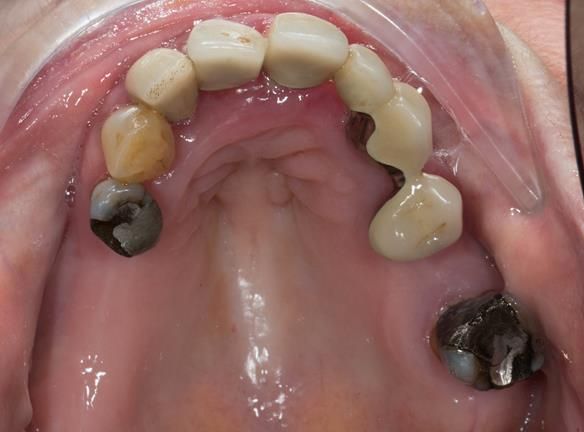

This 73 year old woman was referred to me by her general dental practiioner for treatment.

- The remaining natural upper natural teeth and lower back molars were heavily restored having generalised periodontitis stage 4 Grade C. Some of the teeth exhibited caries. The prognosis for these teeth ranged from dubious to hopeless.

- The upper and lower acrylic based partial dentures exhibited suboptimal extension of the flanges and saddles. They had poor retention, support, stability and tissue fit.

- The patient had a high smile line showing 5mm or more alveolar soft tissue above the upper front teeth during social interaction.